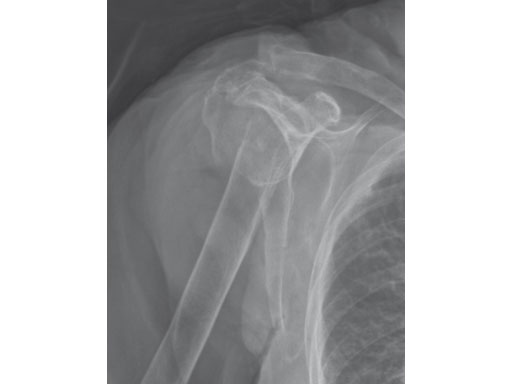

87-year-old woman fell down the stairs, fracture type 12-C1.

Preoperative x-ray.